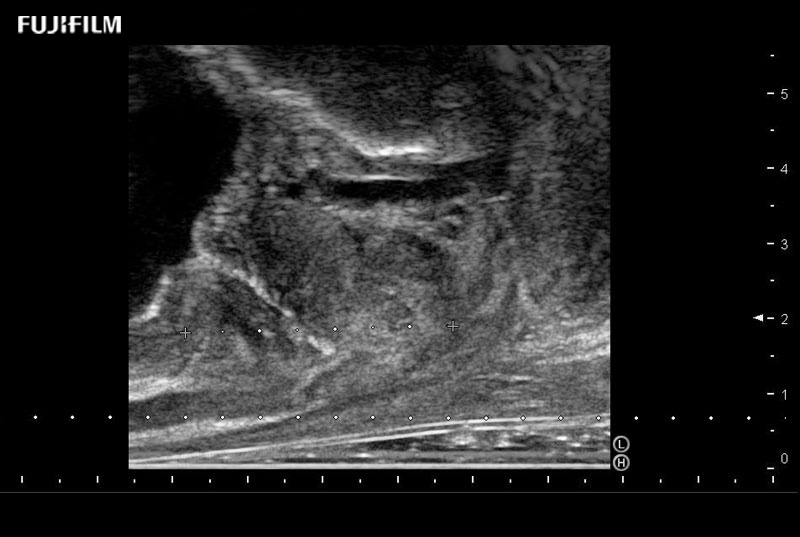

Ideal transducer for Transperineal Biopsy, Hydrogel Spacer Placement, Brachy LDR & HDR, Cryo, and MPMRI procedures.